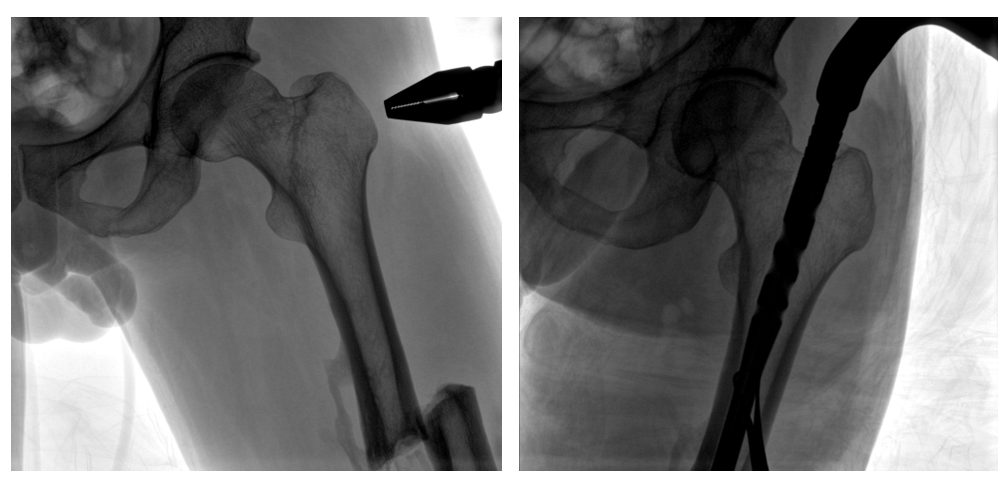

病例二:

患者左股骨干完全骨折,經(jīng)過醫(yī)生評估,使用“髓內(nèi)釘內(nèi)固定術(shù)”進(jìn)行治療。髓內(nèi)釘內(nèi)固定術(shù)需要將入釘點(diǎn)至骨折部位的影像完全展示,在一些長骨的骨折中,對視野范圍要求高。

一體式C形臂釘點(diǎn)至骨折部位的臨床影像

在進(jìn)行髓內(nèi)釘內(nèi)固定術(shù)時,醫(yī)生需要同時觀察到入釘點(diǎn)和骨折部位的情況,PLX119C大平板一體式C形臂能夠呈現(xiàn)更廣闊的成像面積,滿足大部分長骨髓內(nèi)釘內(nèi)固定術(shù)的攝片需求。